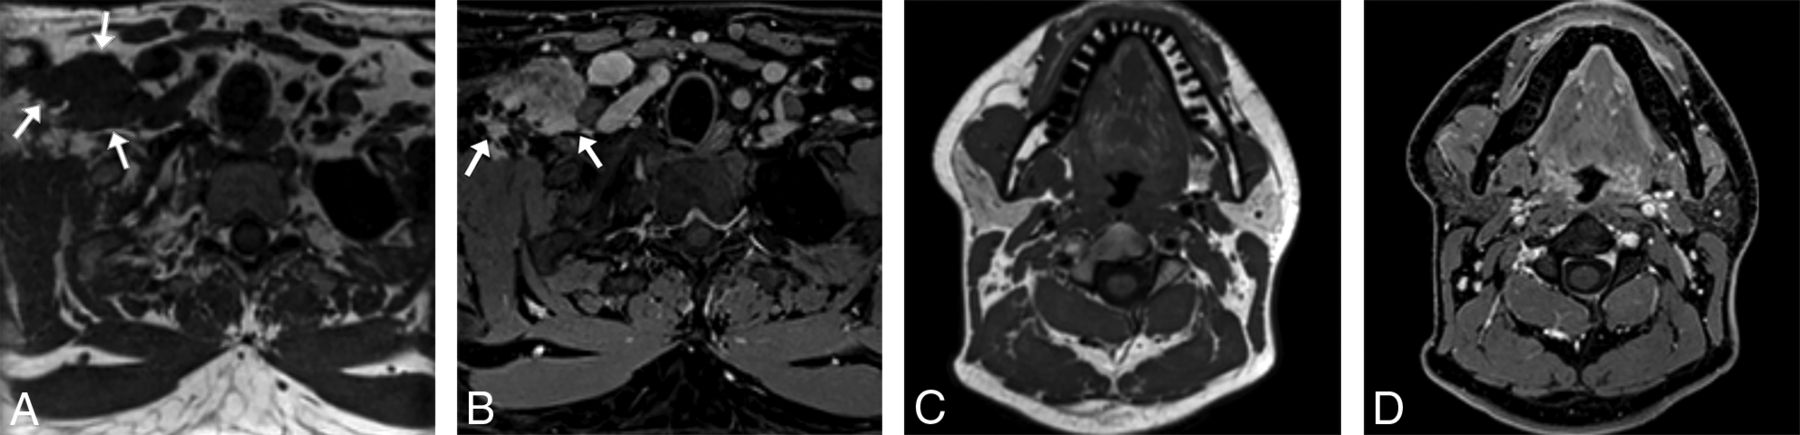

A 27-year-old man with right supraclavicular and chest wall desmoid tumor images on a 1.5T Magnetom Aera system (Siemens). The tumor (arrows) is shown on a general neck protocol, 1.0-mm isotropic sagittal acquisition T1 SPACE axial reformat (A) and T1 VIBE Dixon (B) postcontrast axial reformatted images. Image quality and fat suppression remain good at the level of the thoracic inlet. In addition, T1 SPACE axial reformat (C) and T1 VIBE Dixon (D) postcontrast axial reformat images through the face are provided to show image quality in that region.